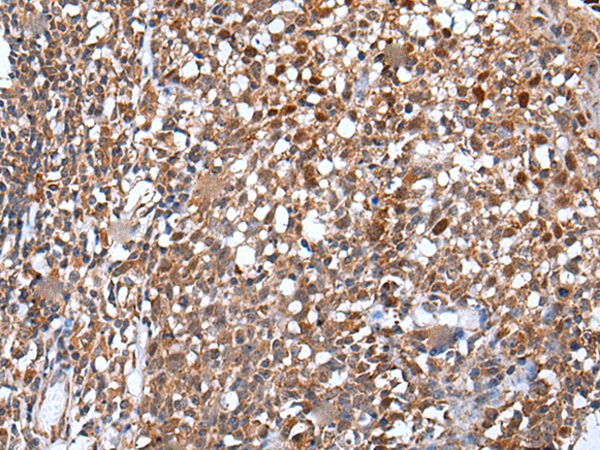

分类: 科研抗体货号: P12875别名: DR11; HH14; BRWD2; WDR15应用: WB,IHC反应种属: Human